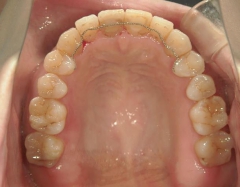

矯正歯科 治療前矯正歯科 治療前

矯正_灰色.pngno.37_7548_治療前_上.JPG矯正_灰色.png

no.37_7548_治療前_右.JPGno.37_7548_治療前_正面.JPGno.37_7548_治療前_左.JPG